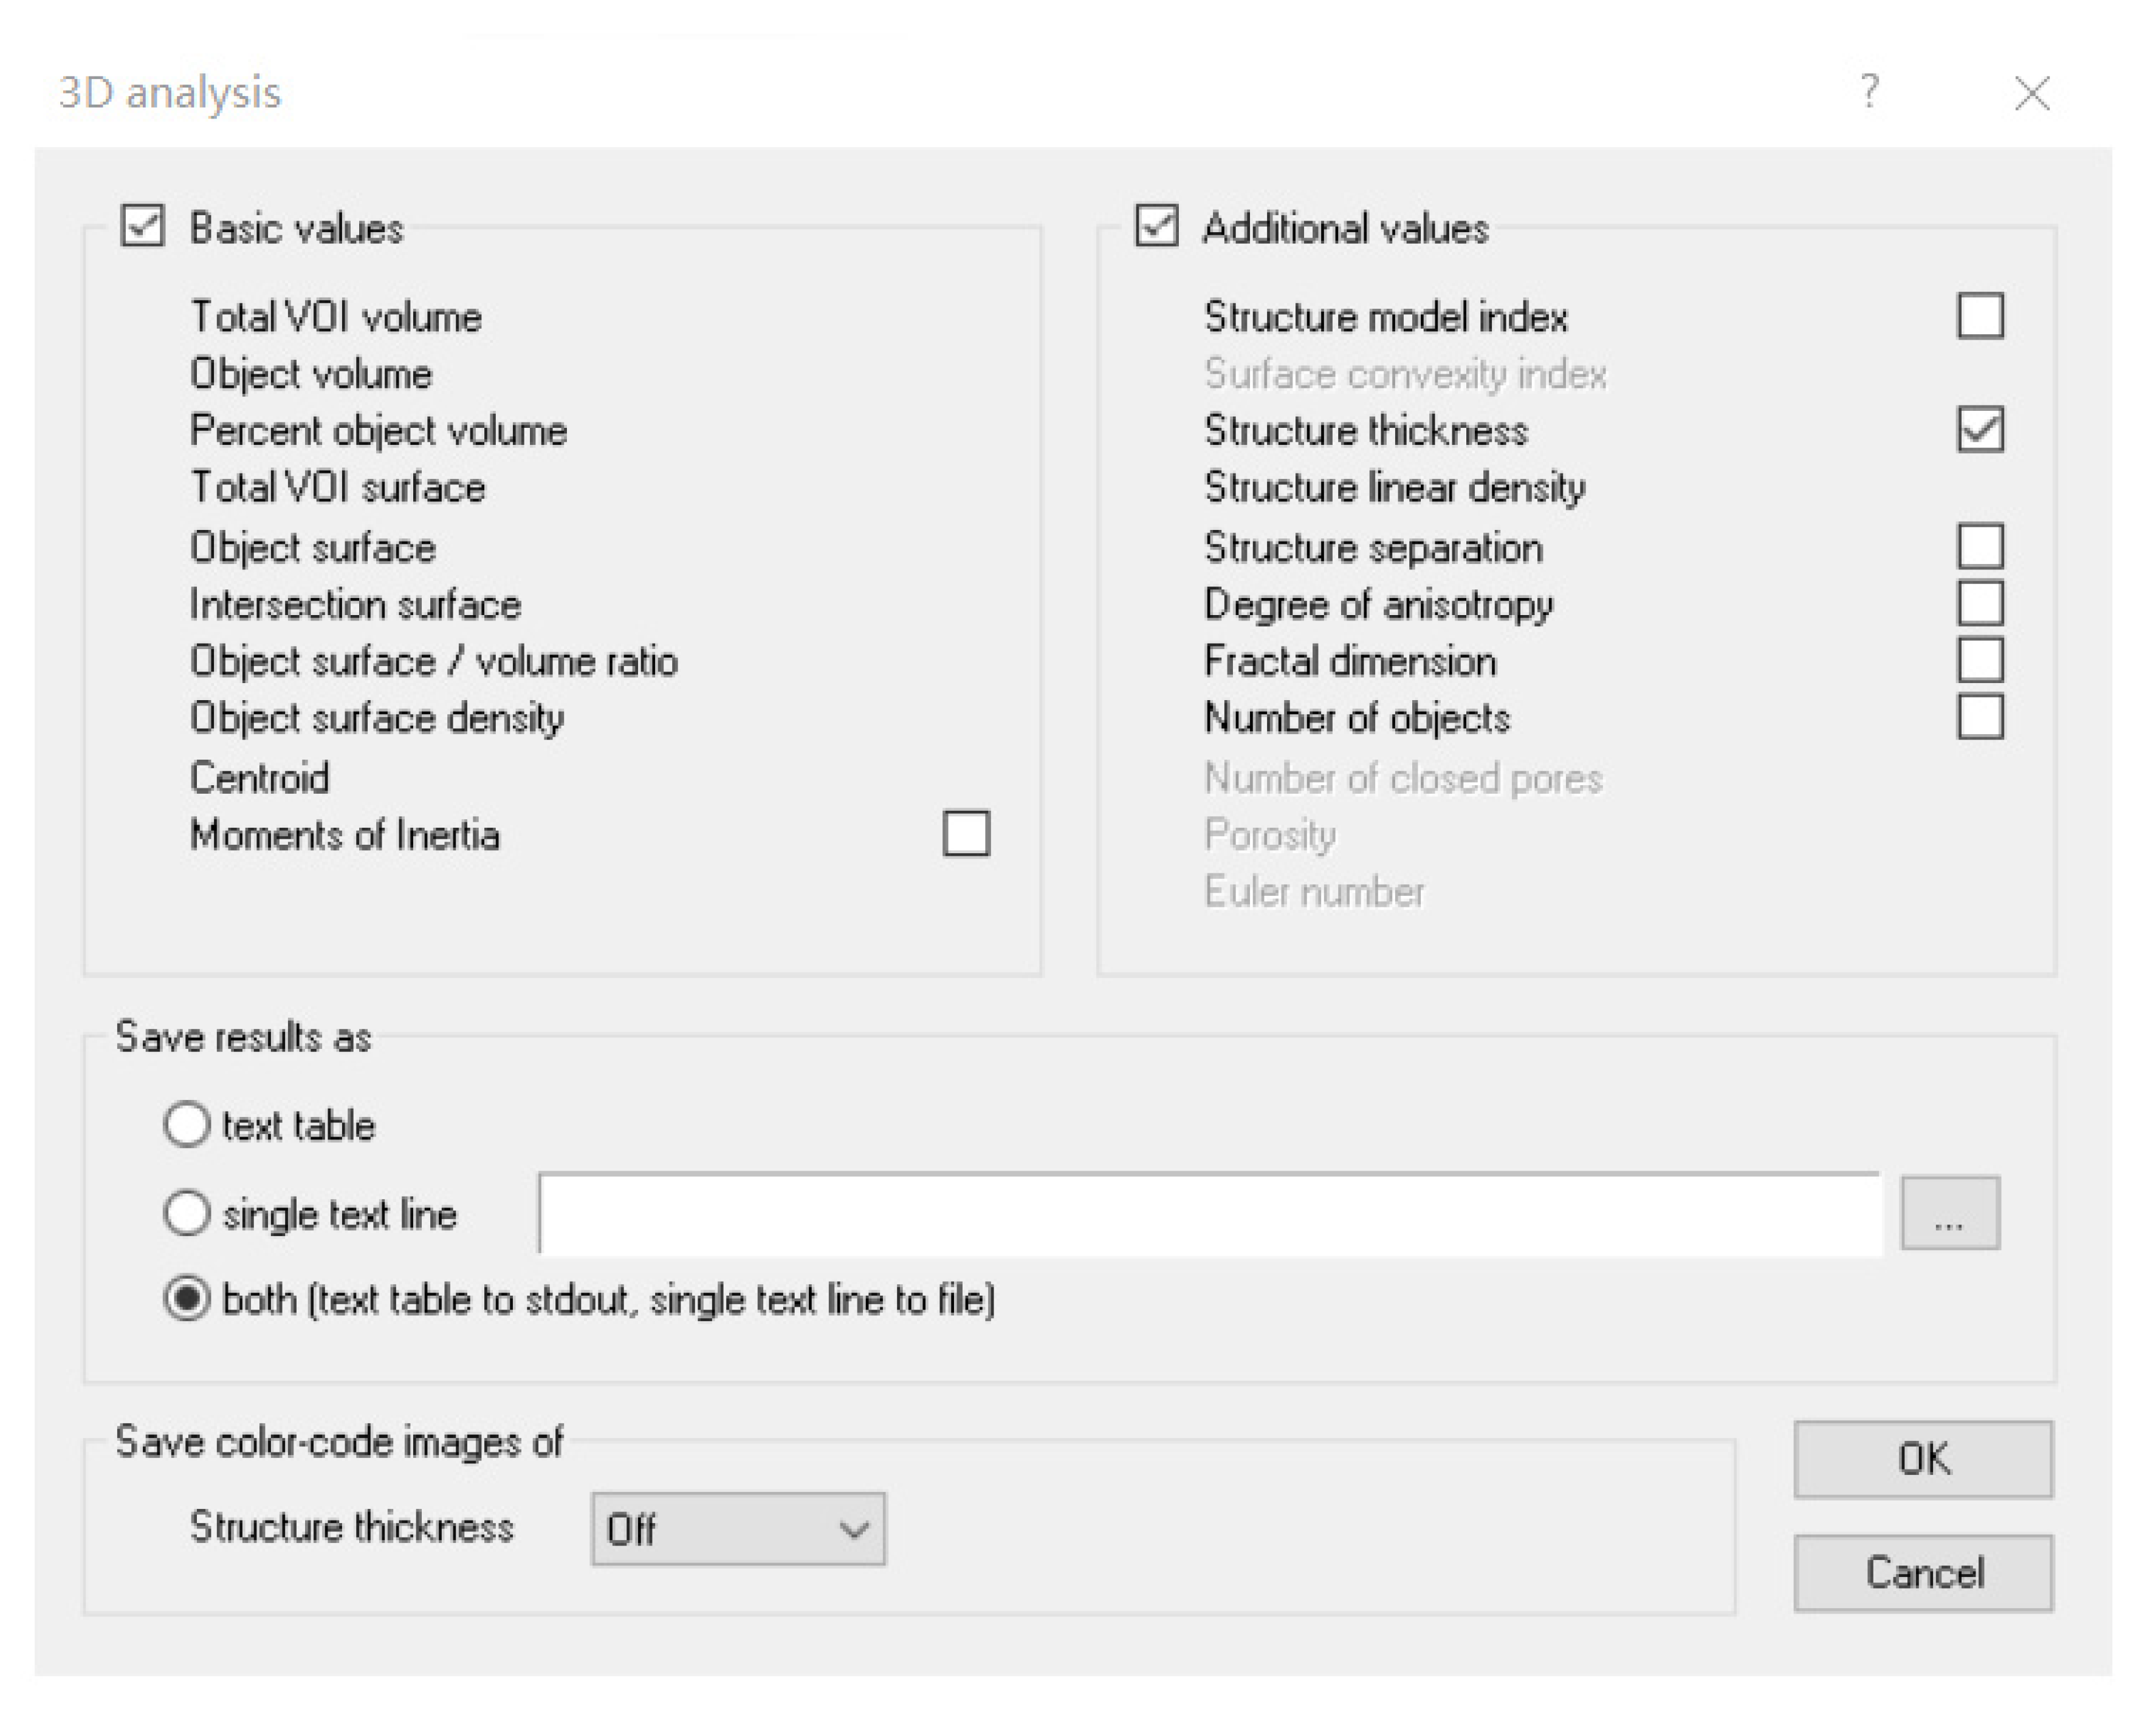

3.4. Quantitative Calculation of Trunk Adipose Tissue

| Description | Tissue Volume (TV) | Object Volume (Obj.V) | Percent Object Volume (Obj.V/TV) | Structure Thickness Distribution (St.Th) |

|---|---|---|---|---|

| Unit | mm3 | mm3 | % | mm |

| 385.62 | 55.91 | 14.49 | 0.3092 |